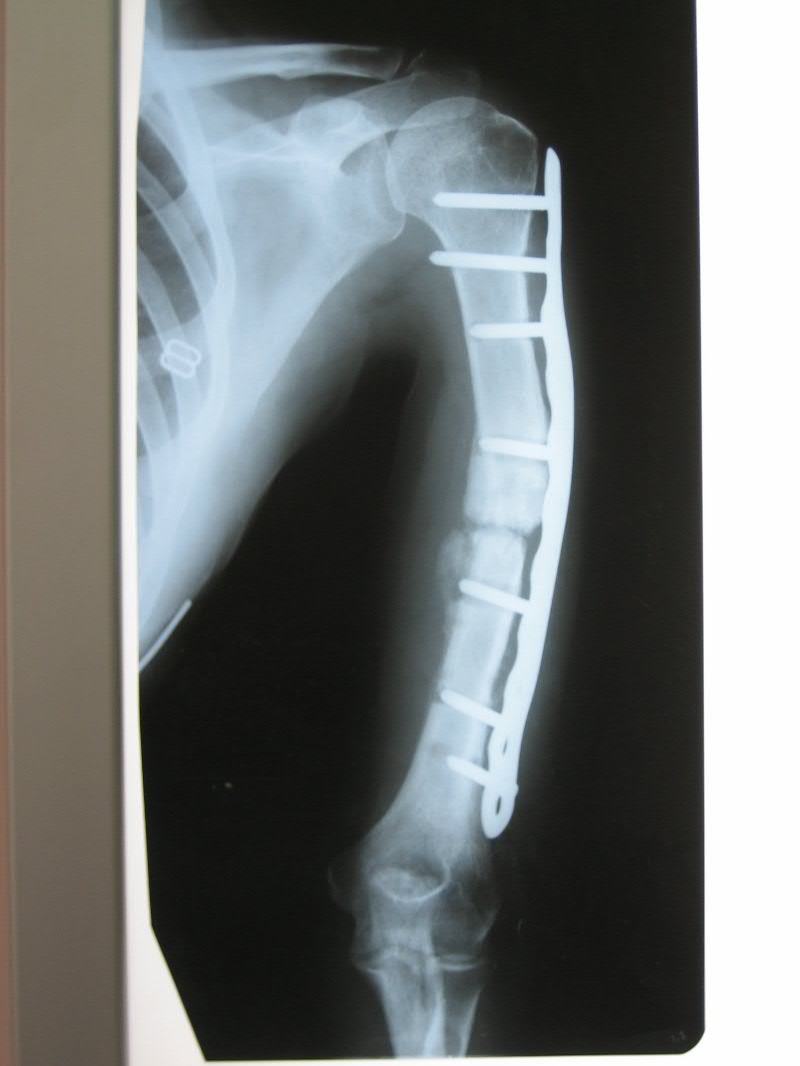

[Ortho] дефект-диастаз левой плечевой кости

п÷п╟я├п╦п╣п╫я┌п╨п╟ п╩п╣я┌ 40.

п■п╡п╟ пЁп╬п╢п╟ п╫п╟п╥п╟п╢ б═- п©п╣я─п╣п╩п╬п╪ п©п╩п╣я┤п╟.

п÷п╬я│п╩п╣п╢п╬п╡п╟я┌п╣п╩я▄п╫п╬ я│я┌п╟п╡п╦п╩п╦ я┌я─п╦ п©п╩п╟я│я┌п╦п╫я▀. п²п╟ п╡я│п╣ - п╬я┌я┌п╬я─п╤п╣п╫п╦п╣ п╪п╣я┌п╟п╩п╩п╟.

п║п╣п╧я┤п╟я│ - п╢п╣я└п╣п╨я┌-п╢п╦п╟я│я┌п╟п╥+я┐п╨п╬я─п╬я┤п╣п╫п╦п╣. п║я┐п╪п╪п╟я─п╫я▀п╧ п╢п╣я└п╣п╨я┌ п╬п╨п╬п╩п╬ 6 я│п╪. п■я▀я─п╨п╦ п╬я┌ п╡п╦п╫я┌п╬п╡. п≤п╫я└п╣п╨я├п╦п╦ п╫п╣я┌.